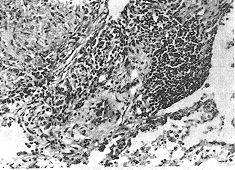

图1 霉草尘肺 肺泡腔内多数巨噬细胞,个别在其胞浆内见

有霉菌孢子,间质纤维化,细支气管亦有增生 HE×100

右下叶肺,实质内有灰白色界限不清的实变区(2cm×1cm),余肺有散在1~2mm病灶,质软,轻度肺气肿。镜下见部分肺泡腔内积大量巨噬细胞,周围明显纤维性增生,间质内尚有淋巴细胞等浸润并伴胶原纤维增加,部分细支气管腔狭窄,周围亦有纤维化,个别部位见有类结节状病灶,由胶原纤维、毛细血管、炎细胞和纤维母细胞等混合构成。